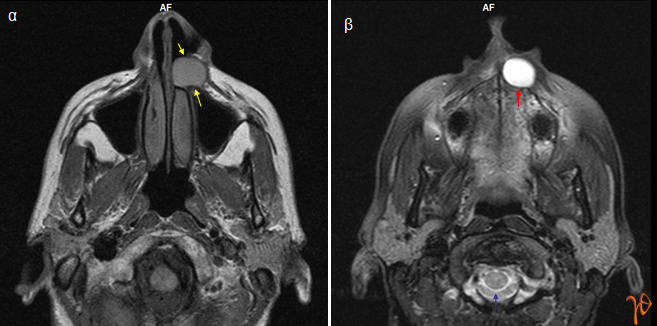

Αντίθετα στην μαγνητική τομογραφία απεικονίστηκε καλώς αφοριζόμενη σφαιροειδής βλάβη μεγίστης διαμέτρου περίπου 2,5 εκατοστών, εδραζόμενη στο χειλικό πετάλο της άνω γνάθου, επί του οποίου είχε προκαλέσει εντύπωμα, και εκτεινόμενη από την αριστερή κάτω ρινική κόγχη μέχρι την μέση γραμμή και μέχρι το ύψος των ακρορριζίων των προσθίων οδόντων(Εικόνες 3 και 4).

Εικόνα 3α: Εγκάρσια τομή(Τ1 ακολουθία) όπου η βλάβη δείχνει να αφορίζεται σαφώς (βέλη), 3β: Εγκάρσια τομή(Τ2 ακολουθία) όπου απεικονίζεται το οστικό εντύπωμα που προκαλεί η βλάβη(κόκκινο βέλος) της οποίας το περιεχόμενο έχει την ίδια ένταση σήματος με εκείνην του ΕΝΥ(μπλέ βέλος).